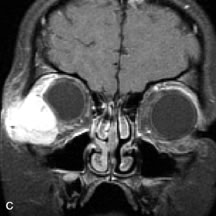

Breast carcinoma metastatic to the orbit has been demonstrated to be hypointense to the surrounding orbital fat on T1-weighted studies and hyperintense on T2-weighted images and has an affinity to the extraocular muscles (Fig. 20).50,64 The MRI characteristics of prostate carcinoma metastatic to the orbit have been described as involving the greater and lesser wing of the sphenoid, orbital roof, and optic canal. Diffuse bone hypertrophy with isointense or slightly hyperintense tissue on T1-weighted images represents the osteoblastic carcinomatous bone infiltration. Contrast enhancement is variable on T1-weighted and fat-suppressed images.65

Fig. 20. A. T1-weighted MR scan demonstrates nodular enlargement of both medial rectus muscles (arrows). B. T1-weighted fat-suppressed contrast-enhanced scan confirms the presence of small metnstatic deposits within the muscles (open arrows).